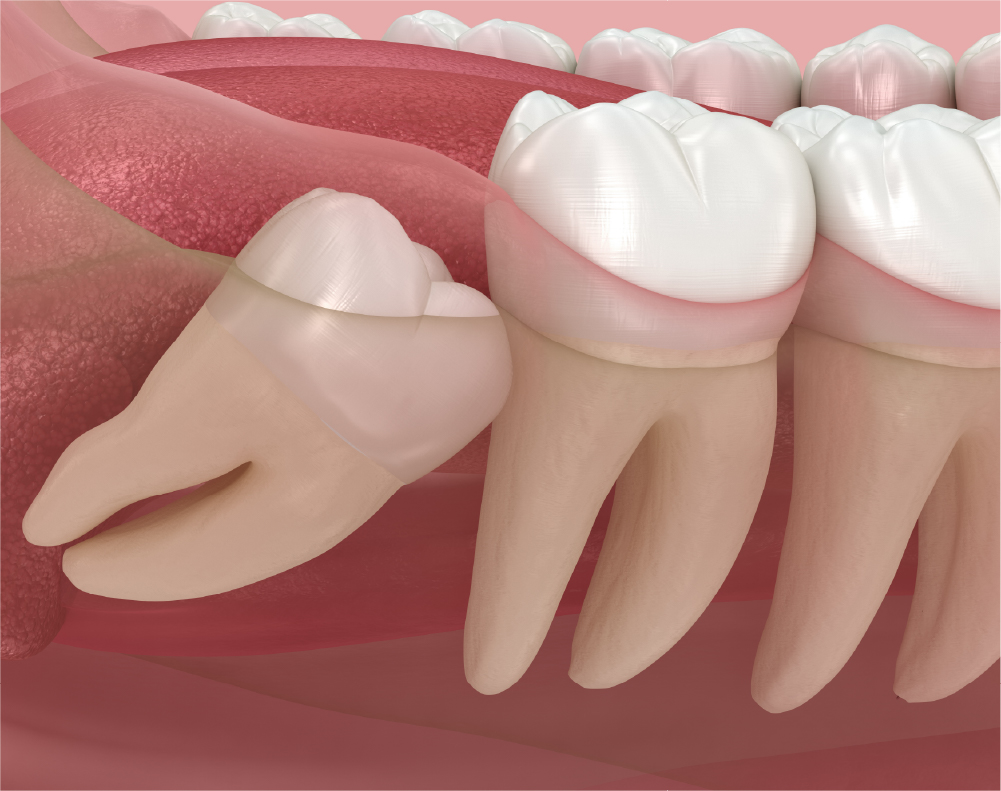

2. 横向きや斜めに生えている場合

• 横向きに生えることで隣の歯を圧迫し、歯並びが乱れる

• 食べ物や細菌が溜まりやすく炎症(智歯周囲炎)を繰り返す